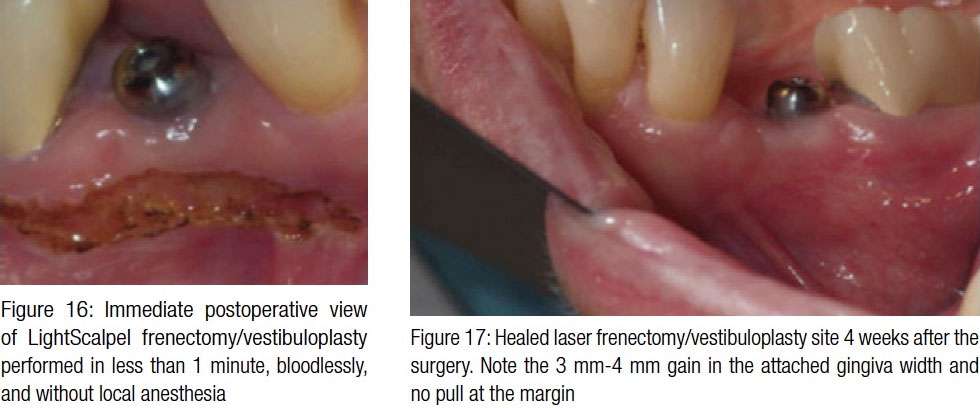

The 73-year-old female patient had a single implant on tooth No. 29 placed. Figures 15A and 15B show a noticeable buccal frenum pull present in the region. High mucogingival junction (evident in Figure 15B) indicates insufficient amount of keratinized attached gingiva. It was decided to perform a CO2 laser frenectomy/vestibuloplasty to increase the width of the attached gingiva. The laser procedure was performed utilizing the same laser settings and following the same protocol as previously described in Case study 1:

Follow-up evaluation: At 4 weeks, the surgical site appeared completely healed (Figure 17). The patient gained 3 mm-4 mm of the vestibule depth, and although the frenum was still present, its attachment moved apically and further away from the implant (Figure 17).